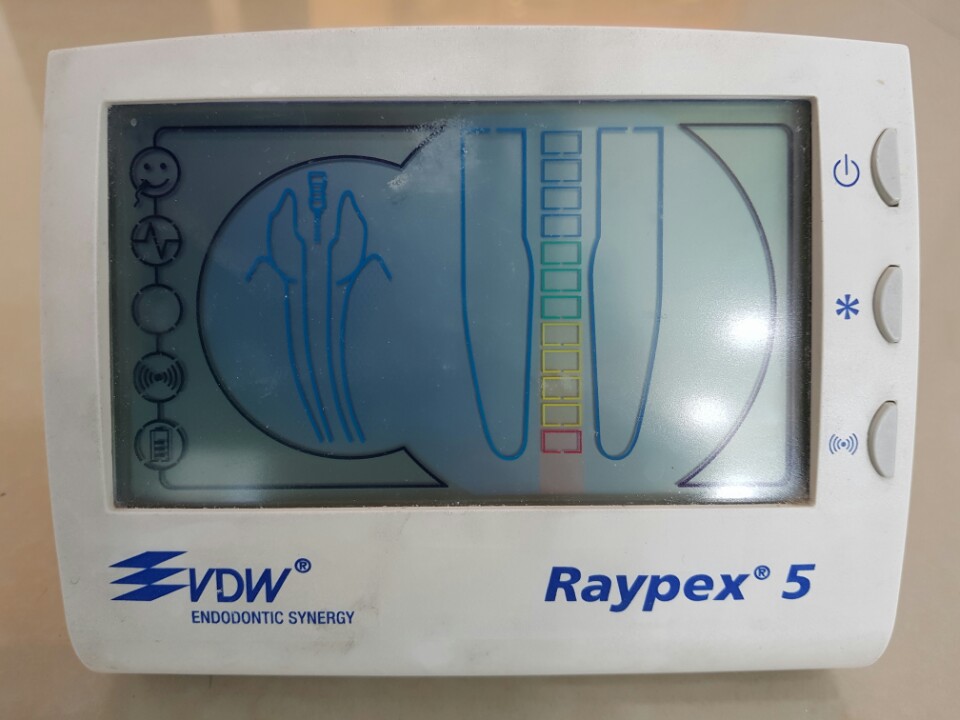

전기 근관장 측정기 (Raypex)

웰플란트 치과는 신경치료 시에 엑스레이만을 참고하여 짐작으로 적당히 진료하지 않습니다. 독일제의 전기 근관장 측정기 Raypex를 이용하여 신경관 길이를 정확하게 측정하고 최상의 치료가 되도록 늘 최선을 다합니다.